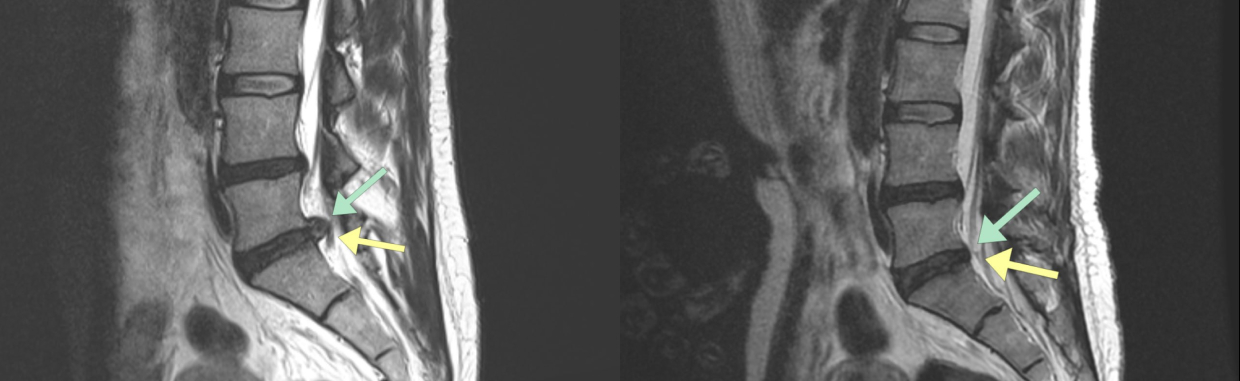

Результаты лечения наших пациентов подтверждаем на МРТ

94% пациентов вылечились без операции.

До лечения

Пациент 42 года.

Ноябрь 2024 года: резкий прострел в спине. Классическое лечение временно снизило боль.

— Через 3 недели произошло сильное обострение с выраженной отдачей боли в ногу.

— Появились серьёзные ограничения: невозможно сидеть, трудно надеть обувь, уже через 20 метров ходьбы возникала нестерпимая боль в ноге. Прежние препараты перестали помогать.

После лечения

Апрель 2025 года. Сильные боли полностью прекратились примерно 3,5 месяца назад. Подвижность восстановилась в полном объёме, ограничения в движениях отсутствуют. Из симптомов сохраняется лишь лёгкое онемение в ноге, которое постепенно уменьшается и может сохраняться до 6 месяцев.